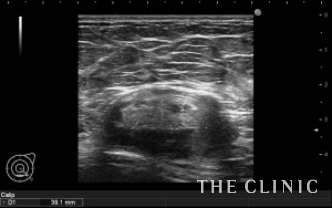

エコーにて、右にオイルシスト、左にオイルシストと4㎝の混合性腫瘤を認めました。(オイルシストの症例はNo.32でご紹介します)

混合性腫瘤の被膜が非常に硬く、中々カニューレが被膜を破れませんでした。何とか突き破ることが出来、ベイザーリポで崩していきます。